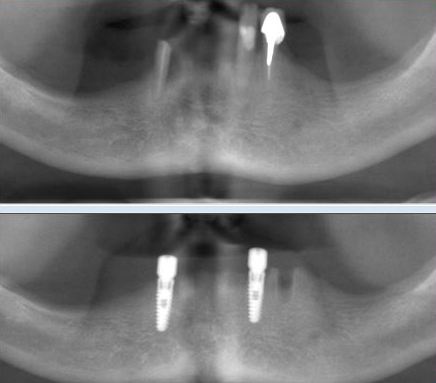

DENTURE STABILIZATION

This patient’s existing old partial denture became loose after one of her teeth had broken. After thorough dental examination Dr. Andrews recommended to extract remaining lower teeth and immediately place two regular size dental implants in order to stabilize a new full lower denture.

During only one surgery three lower teeth were removed, two dental implants were placed. Three months later two snap-on attachments were placed on the integrated implants.

Her speech and chewing ability has instantly significantly improved. The satisfied patient regained quality of life she desired and expressed desire to replace the old upper denture with a new one as well.